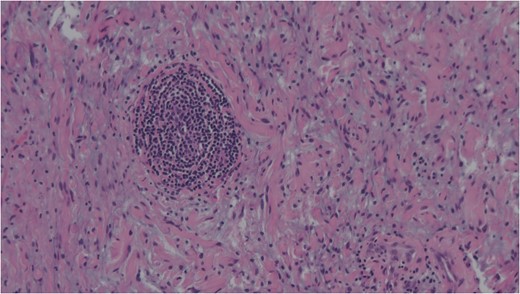

Cells with enlarged hyperchromatic nuclei seen in ancient schwannoma. Haemotoxylin and eosin (H&E).

FNAC remains a valuable tool to characterize neck masses but its accuracy in schwannoma is only reported to be 20–25% [4, 6]. Macroscopically, schwannomas are smooth and uniform and often attached to their nerve of origin which may help intra-operative diagnosis. Histologically, schwannomas are encapsulated and consist of alternating Antoni-A and Antoni-B regions [7]. Ancient schwannomas can be recognized by their additional degenerative features such as fibrosis, cystic necrosis and degenerative nuclei [7]. They can often be mistaken for malignant tumours due to nuclear atypia and hyperchromasia [7].